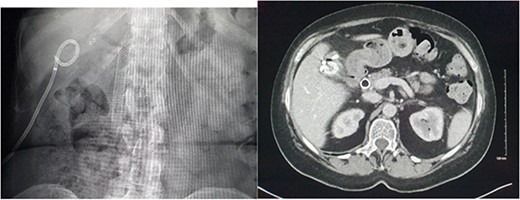

Magnetic resonance imaging (MRI) of the liver and magnetic resonance cholangiopancreatography (MRCP) were performed in the following days, which demonstrated a frank rupture of the gallbladder and a patent biliary tree (Fig. 3). After a few more days, the patient became peritonitic and a further CT was performed. This demonstrated a moderate volume of peritoneal free fluid and haematoma in the gallbladder fossa (Fig. 4). Ultrasound-guided drainage of peritoneal fluid was performed producing bilious fluid. ERCP was performed, which demonstrated ongoing leak from the gallbladder fossa (Fig. 5) and allowed placement of a covered biliary stent to divert flow away from the cystic duct.

CT demonstrating large volume of bilious peritoneal fluid with haematoma and calculus in the gallbladder fossa.